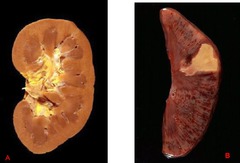

Front

organ? issue?

-Hydropic degeneration of the liver -accentuated lobular pattern; pallor-light pink

Describe this liver